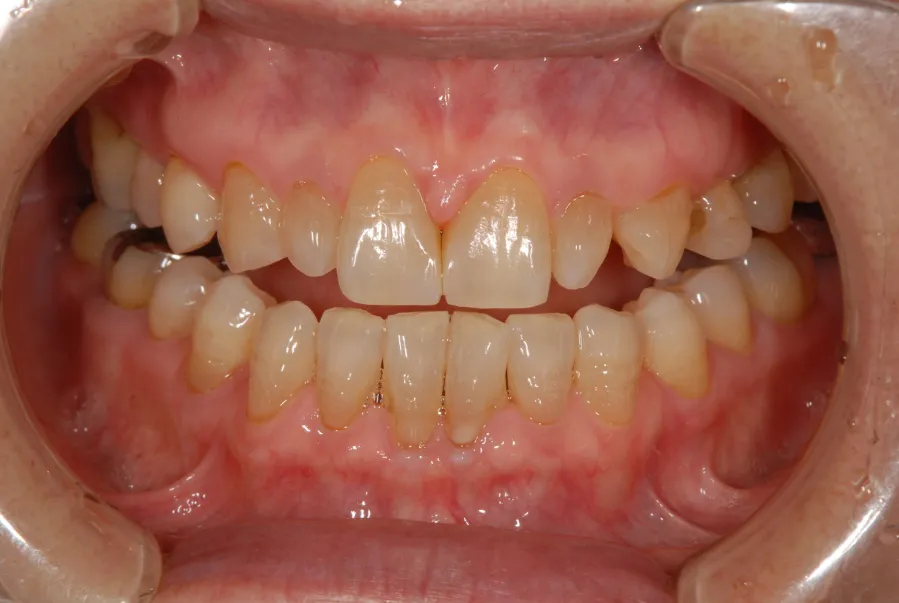

CASE1 60代女性 ダイレクトボンディングによる修復治療

初診

歯石除去で来院されました。

除去後、話を聞くと上顎の前歯の歯と歯の間が離れていることが

以前より気になっていると仰られ、治療計画を立案。

レントゲン写真を撮影。

口腔内写真の撮影

残っている歯の問題点などを解析

顔全体・口元の写真を解析

前方・口元

側方・口元

口腔内の分析・治療計画

さまざまな方向性から、歯のバランスや問題点を解析。

治療計画の立案を行います。

治療後

治療その後

術後4ヶ月